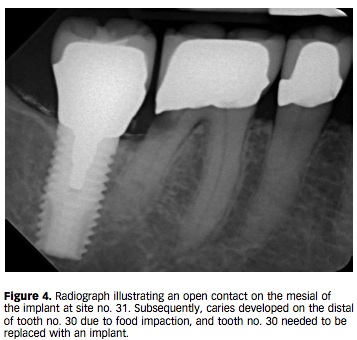

文章一開始就講到因為一般在失去牙齒的時候, 整體上因為咬合力的影響牙齒會向前去移動, 很常在臨床上看到早期缺失6而7就向前傾倒的情形. 這個力量叫做anterior component of force (ACF). 在咬合的時候, 自然牙molar的水平移動56-75um, 垂直移動28um; 植牙的水平移動12-66um, 垂直移動5um. 既然如此, 植牙和自然牙的性質不同, 長期下來可能在植牙的mesial side會出現open contact.

那這樣的open contact的機會有多大?根據這幾年來的paper, 機率高達5-6成. 那要怎麼解決?理想上當然是重新做新的contact, 若是嚴格監控患者是不是能刷乾淨.